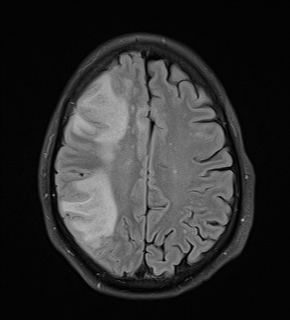

A common virus found in many healthy people can cause a rare but potentially lethal brain disease in those with altered or weakened immune systems. It can strike people with untreated HIV/AIDS and those receiving immune-modifying or suppressive therapies for autoimmune diseases, cancers, and transplants. Among multiple sclerosis (MS) drugs, natalizumab treatment has posed the biggest risk of the brain infection, called progressive multifocal leukoencephalopathy (PML).

No specific therapy exists for PML. Clinical care focuses on reconstituting the immune system, which can further damage the brain by ramping up the immune response against the infection, a process called immune reconstitution inflammatory syndrome (IRIS).

The first report of PML in 1958 described a brain disease with scattered demyelination in three people with Hodgkin’s lymphoma. The viral cause of PML was discovered in 1971 and named JC virus (JCV) for the patient’s initials. PML surged onto the scene in the early days of HIV, when PML became a common and severe opportunistic infection. It was a virtual death sentence for about 5 percent of all people with untreated HIV, which depletes a major type of T cells. Now, antiretroviral therapy has greatly decreased PML cases, but HIV still accounts for the vast majority of deaths due to PML (Gheuens et al., 2013).

PML prevention now relies mainly on prescreening high-risk patients and prescribing natalizumab for only a limited time, as well as close monitoring of people on any drug associated with PML. About three-quarters of people with natalizumab-associated PML have survived the illness, often with irreversible brain damage and disability (Berger, 2015).